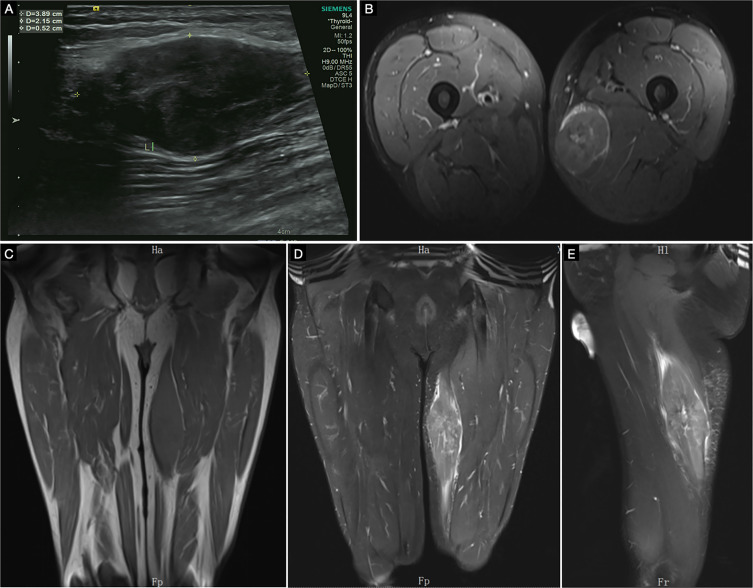

Case presentation: A 60-year-old male patient presented to our hospital two years ago with a painless mass measuring 39×22 mm on the left thigh. He refused treatment due to the absence of discomfort. Over the following two years, the painless mass gradually enlarged. Magnetic resonance imaging (MRI) upon admission revealed a mixed signal, spindle-shaped shadow measuring approximately 170 mm × 50 mm × 55 mm in the left femur's subcutaneous soft tissue, accompanied by mild surrounding swelling. Surgical resection was performed. Microscopic examination revealed round or polygonal tumor cells distributed in sheets or nests, with no evident atypical cells or signs of nuclear division. Immunohistochemistry demonstrated positive staining for S100, SOX-10, Vimentin, NSE, CD56, and H3K27Me3 in the tumor cells, with a Ki-67 labeling index of approximately 15%. The postoperative pathological diagnosis confirmed giant GCT.